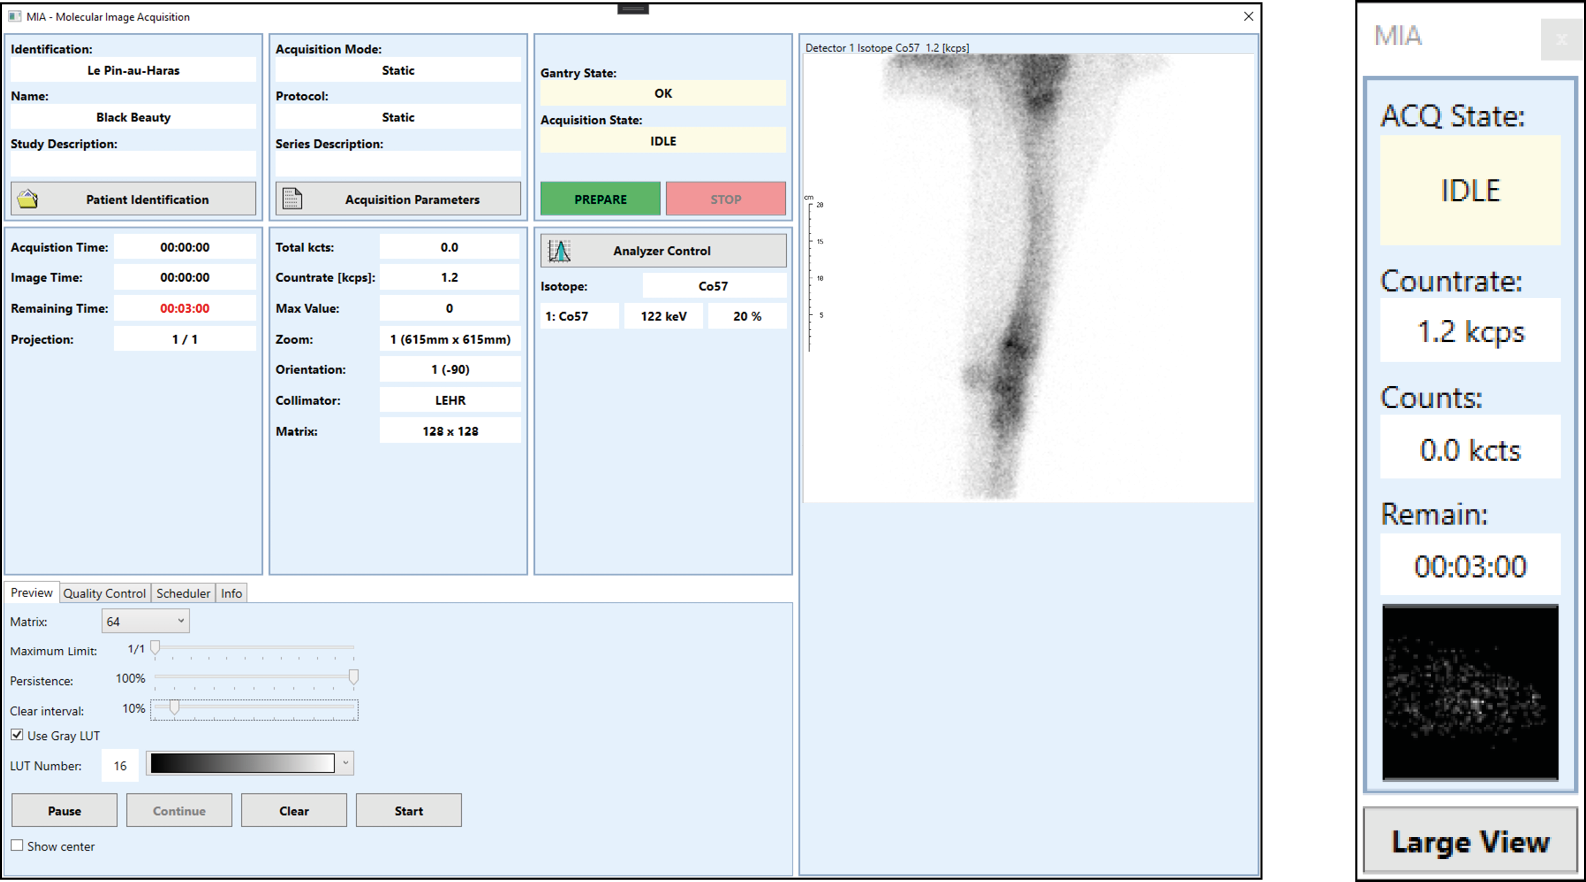

- MiA Software with New User Interface

MiA - Clear and Versatile Application Software